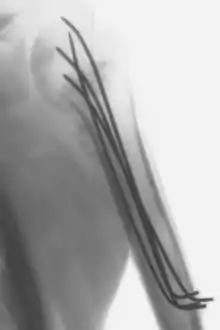

Intraoperative X-ray of a humerus fixated by Kirschner wires